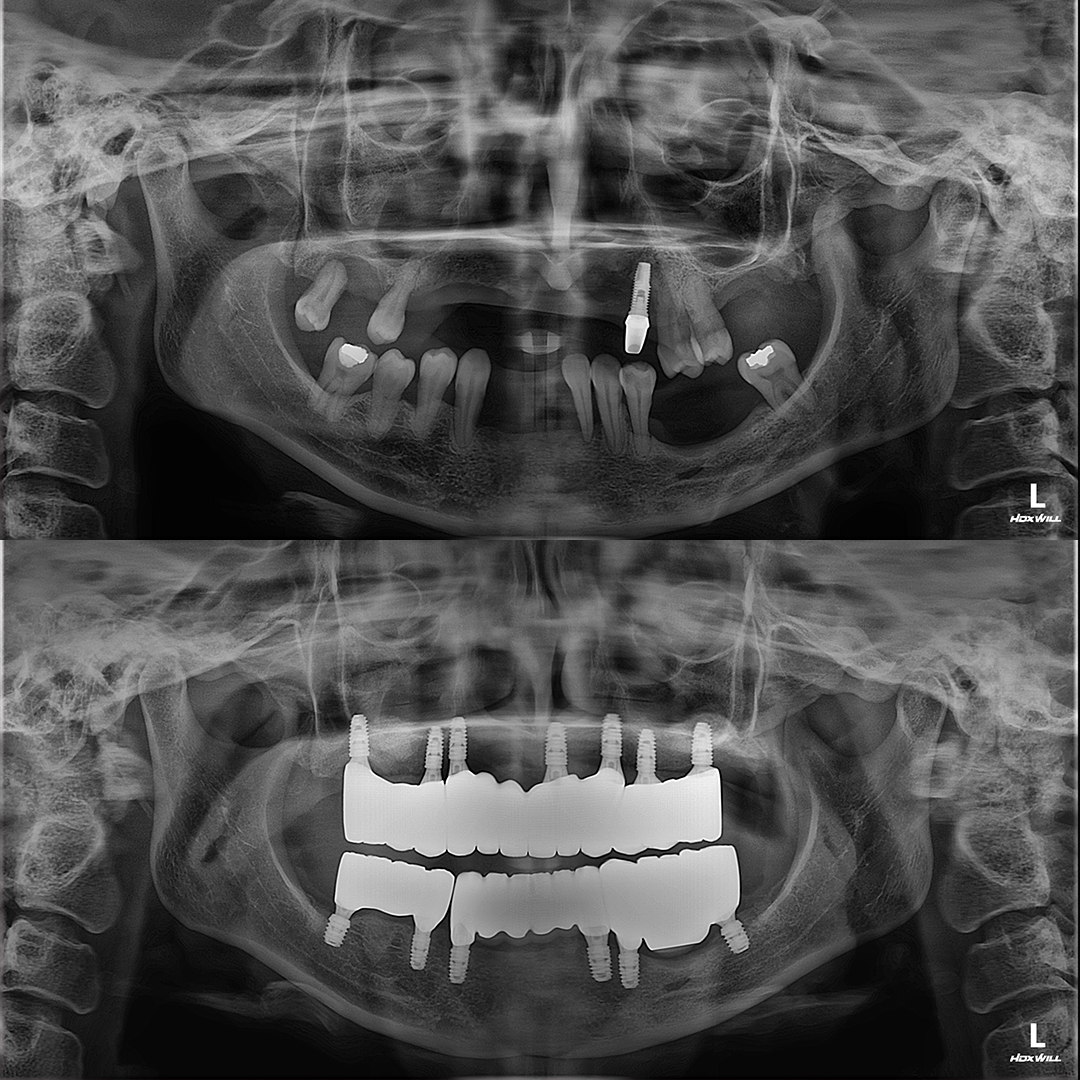

평균 악당 30분의 빠른 식립시간, 치료 케이스 다수 보유

전체 임플란트

상·하악 전체 치아를 대체하는 임플란트로 최소한의 식립을 통해

자연치아와 비슷한 기능을 수행할 수 있도록 합니다.